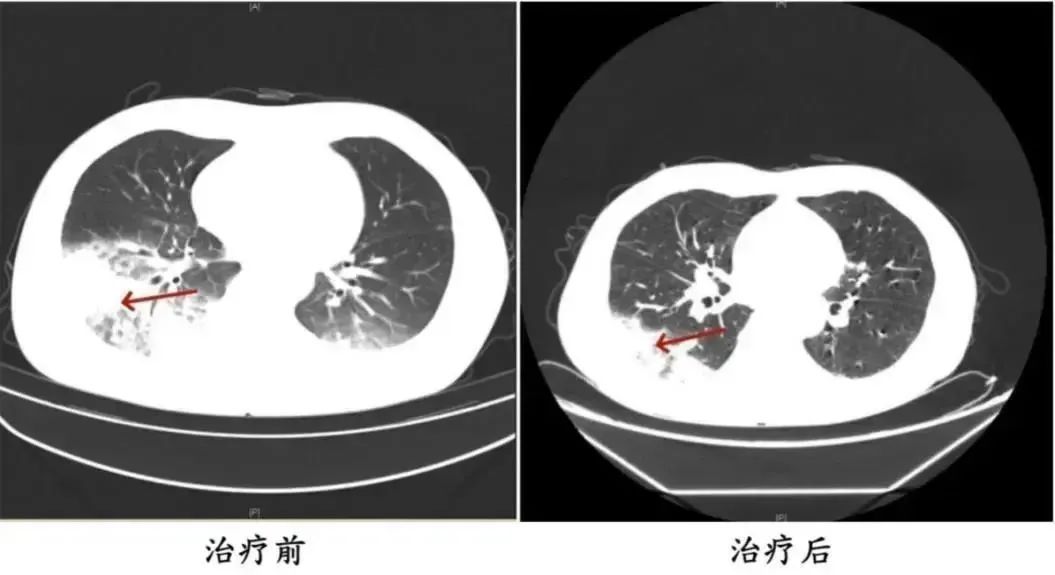

胸部CT显示李先生的左肺已出现大面积白色影像,几乎占据一半肺部。经过肺泡灌洗NGS检测,最终确认“罪魁祸首”是嗜肺军团菌。

李先生肺部治疗前与治疗后的对比